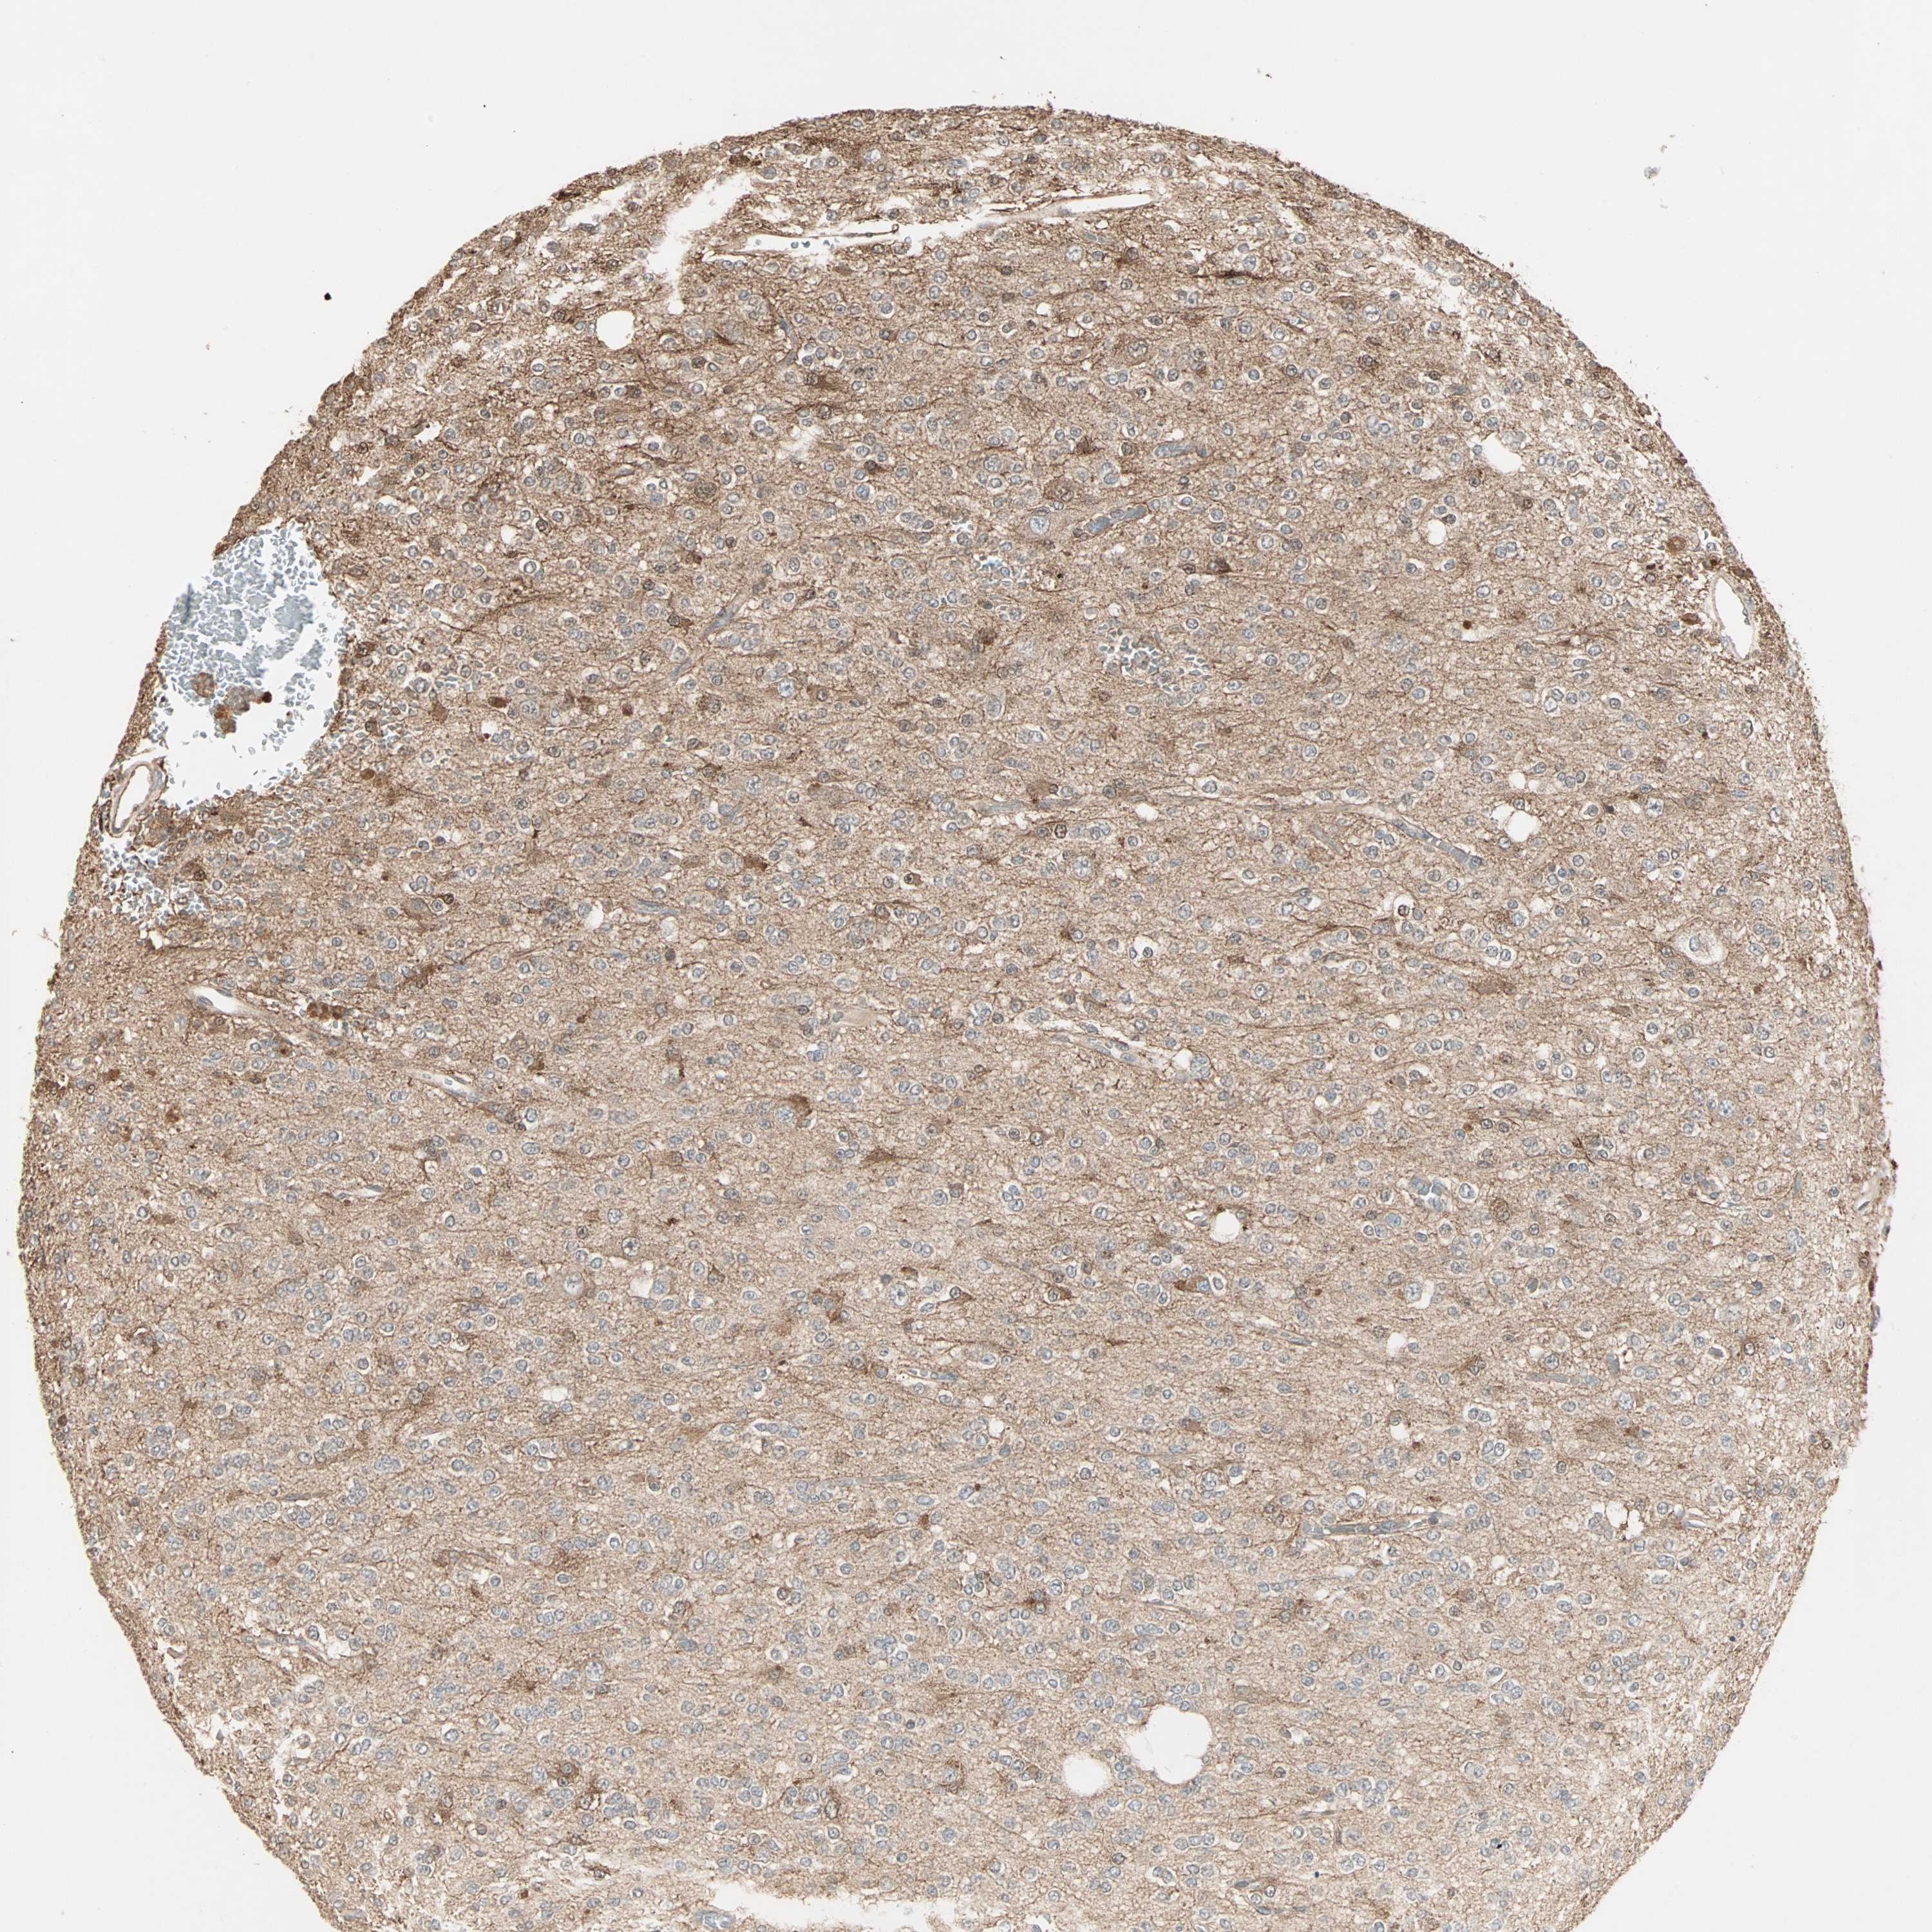

GLIOMA - Protein expressioni

A mouse-over function shows sample information and annotation data. Click on an image to view it in a full screen mode. Samples can be filtered based on level of antibody staining by selecting one or several of the following categories: high, medium, low and not detected. The assay and annotation is described here.

Note that samples used for immunohistochemistry by the Human Protein Atlas do not correspond to samples in the TCGA dataset.

Antibody stainingi

Antibody staining in the annotated cell types in the current human tissue is reported as not detected, low, medium, or high, based on conventional immunohistochemistry profiling in selected tissues. This score is based on the combination of the staining intensity and fraction of stained cells.

Each image is clickable and will lead to virtual microscopy that enables deeper exploration of all samples and also displays staining intensity scores, fraction scores and subcellular localization as well as patient and tissue information for each sample.

Antibody HPA007716

Staining

High

Medium

Low

Not detected

Intensity

Strong

Moderate

Weak

Negative

Quantity

>75%

75%-25%

<25%

None

Location

Nuclear

Cytoplasmic/membranous

Cytoplasmic/membranous,nuclear

Glioma, malignant, Low grade

Glioma, malignant, High grade